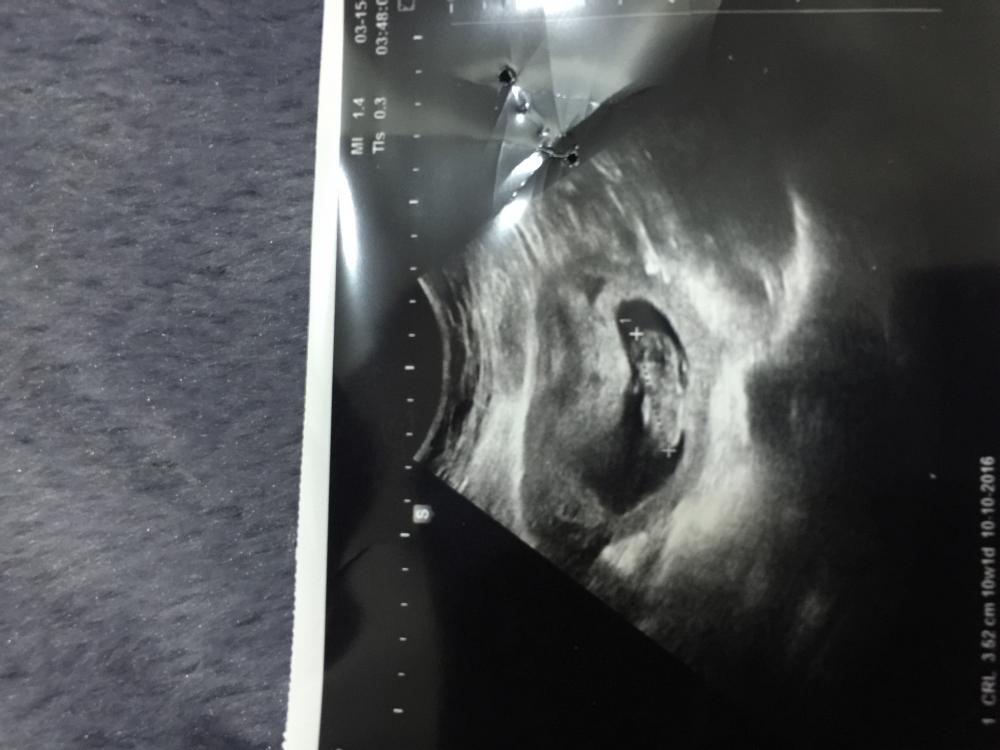

اخت رنا شوفي صوره السونار والله تعبت ع مانزلت اذا مو واضح خبريني لان مدري كيف نزلت السونار ع حساب الدوره اخر اسبوع الثامن وع حساب السونار الاسبوع العاشر ياليت تخبريني وجزاك الله خير